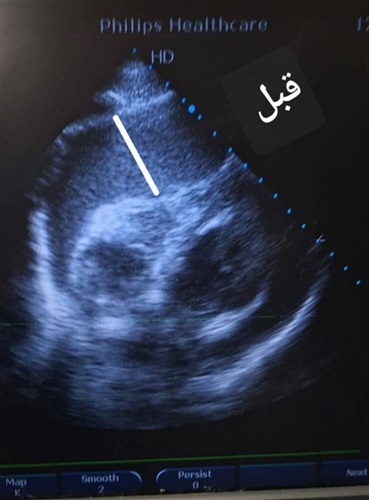

ومع المتابعة الدقيقة والمرور الطبي المنتظم، لاحظ الأطباء ارتفاعًا حادًا في معدل نبضات القلب، ما استدعى تحركًا فوريًا وإجراء رسم قلب كهربائي (ECG) وفحص الموجات الصوتية على القلب (Echocardiography)، لتكشف الفحوصات عن ارتشاح بالغشاء التاموري مصحوب بتأثير ضاغط على عضلة القلب، وهي حالة حرجة تتطلب تدخلًا عاجلًا دون أي تأخير.

وأسفر التدخل الدقيق والسريع عن سحب ما يقرب من 700 مل من السوائل من الغشاء التاموري، وهو ما انعكس مباشرة على الحالة العامة للمريض، حيث ارتفعت نسبة تشبع الأكسجين واستقرت العلامات الحيوية بصورة ملحوظة، في مشهد جسّد بوضوح قيمة القرار الطبي السريع المبني على خبرة علمية وتكامل مهني.